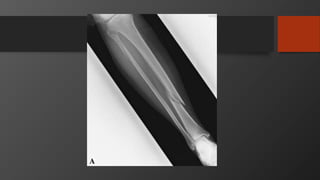

Tibia Shaft Fractures

• Mechanism

• Low energy usually torsional injury

• High energy, e.g. road-traffic accident

• Presentation

• Swelling

• Pain

• Inability to bear weight

• Always rule out open fractures

• Always check for compartment syndrome

• Always check neurovascular status

Tibial Plateau Fracture

• Imaging:

• X-Ray: AP, Lateral

• Full length

• Knee and ankle also